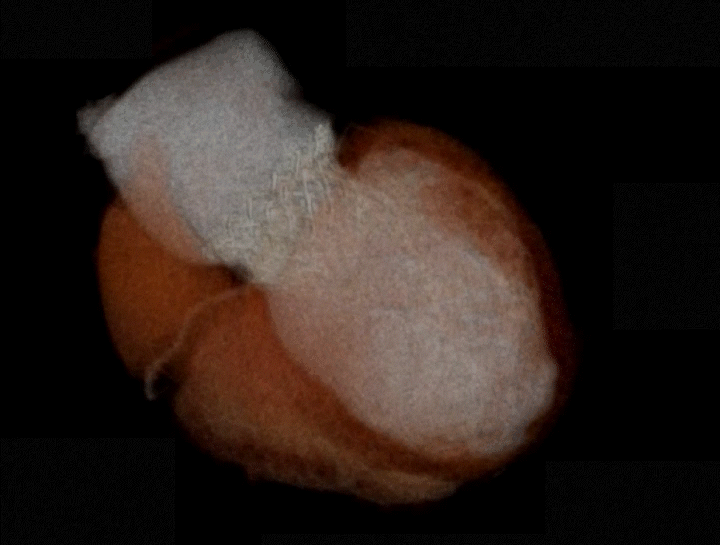

该手术采用左侧第五肋间微创切口心尖入路,透视下经导丝置入输送系统,逐步释放瓣膜。透视及TEE确认瓣膜位置满意后撤出输送系统,二尖瓣瓣膜形态及工作状态良好,复查左心室造影,提示无瓣周漏,无左室流出道梗阻,左右冠状动脉显示良好,未受任何影响。

患者术后30天随访状态良好,随访显示左心室逆重构,左心室功能伴左心室结构显著改善,全面达成包含二尖瓣反流程度降低、心功能改善等有效性指标。人工二尖瓣工作正常,支架结构及形态稳定,锚固良好无位移,无瓣周漏。瓣叶开闭形态良好,血流动力学表现优异,平均跨瓣压差仅1mmHg。

心通医疗潜心多年完全自主研发的经导管二尖瓣置换系统,其设计理念来源于对临床需求的深刻理解以及多项关键技术的突破,该系统同时拥有经心尖及经房间隔入路途径,可适配32Fr经房间隔输送系统。

简明的人工瓣膜设计大大降低了该系统手术操作难度及左室流出道梗阻风险,同时实现优异的血流动力学表现及出众的锚固性能。该产品亦首次应用心通医疗自研的抗钙化以及干瓣处理工艺,去除瓣膜材料游离钙化位点,具备更好的抗钙化性能,从而进一步提高瓣膜的耐久性。